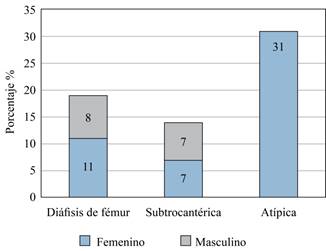

Se analizó un total de 441 registros clínicos, de los cuales 98 (22.2%) eran del sexo masculino y 343 (77.7%) del femenino. Posterior a la revisión de los estudios radiológicos y clasificación de la ubicación de las fracturas en el fémur, se constató un total de 51 FS/FD. Tras la aplicación de los criterios de definición de FAF, se determinó la existencia de 31 casos (Figura 3).

Figura 3: Distribución de fracturas subtrocantéricas y diafisarias de fémur de trazo atípico y trazo no atípico, en pacientes mayores de 40 años estratificado por sexo.

En el caso de distribución por sexo, las FAF fueron exclusivas del sexo femenino, mientras que las FD y FS se presentaron tanto en el sexo masculino como en el femenino (Figura 5).